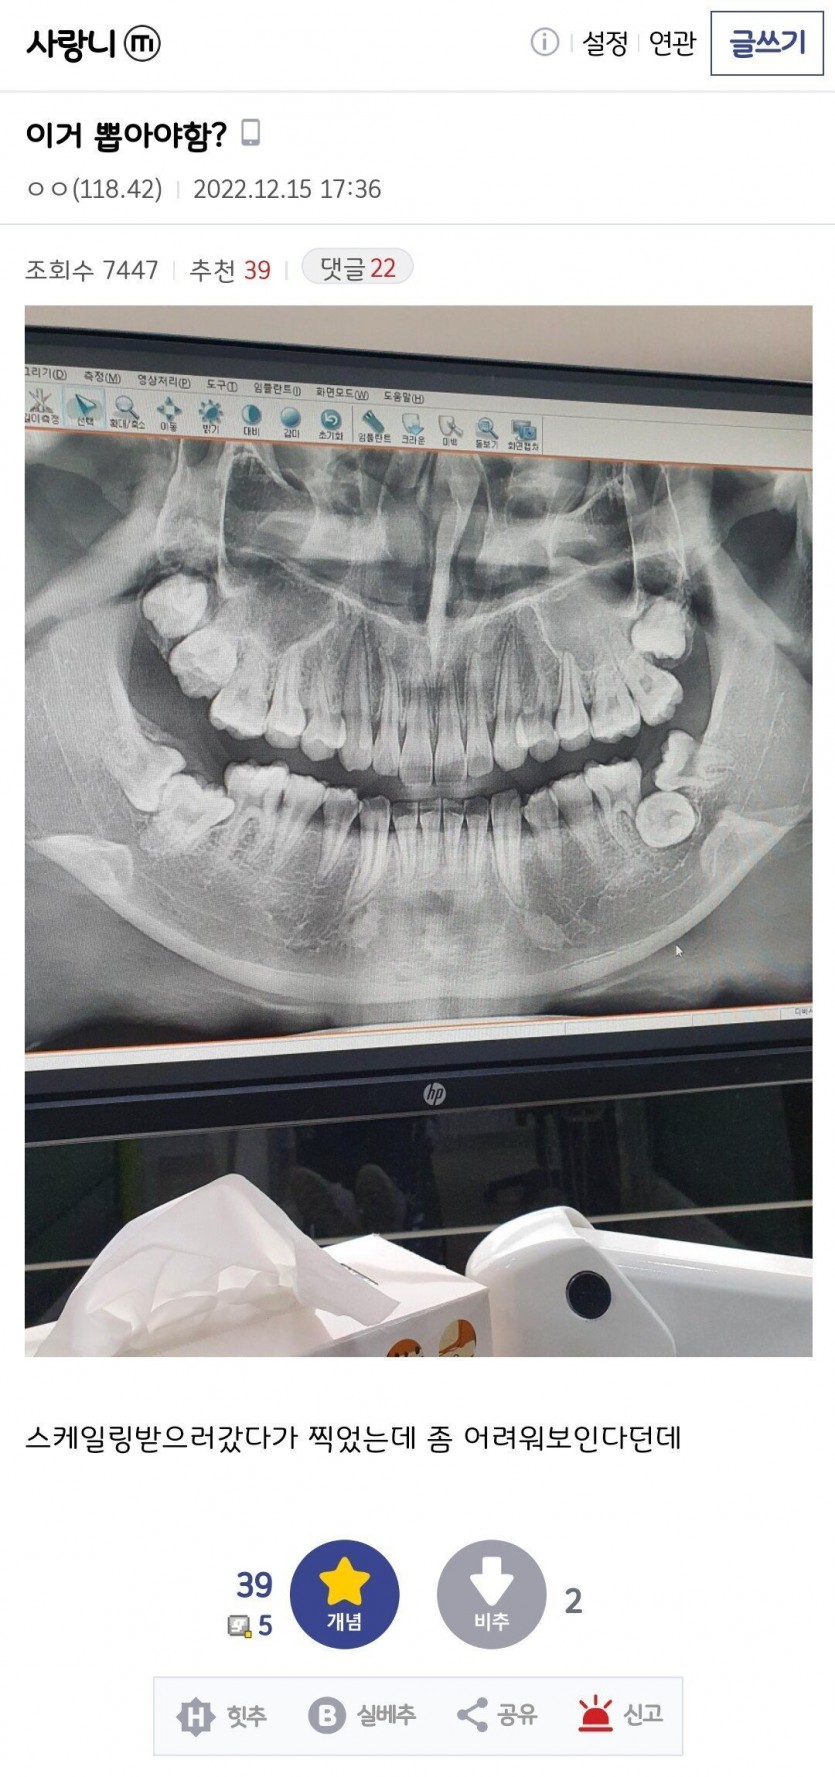

본문